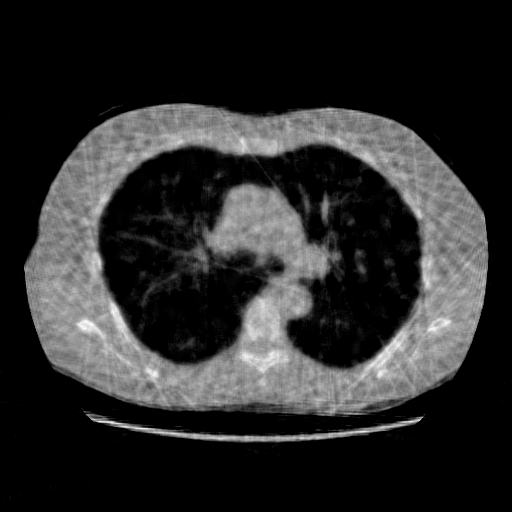

IV-F Real CT Reconstruction

To further verify the effectiveness of the RBP-DIP framework, real CT data from the Finnish Inverse Problem Society [49, 50] was used to validate our algorithm. The few-view and limited-angle reconstruction results are shown in Figure 12. Due to the lack of available training sets, pre-trained models were not included in the experiments. Different from the previous experiment, data from Finnish Inverse Problem Society is highly noisy. However, it is still evident that the RBP-DIP outperforms all other algorithms in all experiments, even under high noise and highly ill-posed conditions.

SNR/SSIM

10.94dB/0.41

13.60dB/0.40

16.25dB/0.53

10.79dB/0.45

13.91dB/0.47

16.49dB/0.57

9.74dB/0.30

12.22dB/0.26

14.46dB/0.42

(a) Reference

8.41dB/0.34

(b) ASD-POCS

12.77dB/0.31

(c) DIP

14.59dB/0.45

(d) RBP-DIP